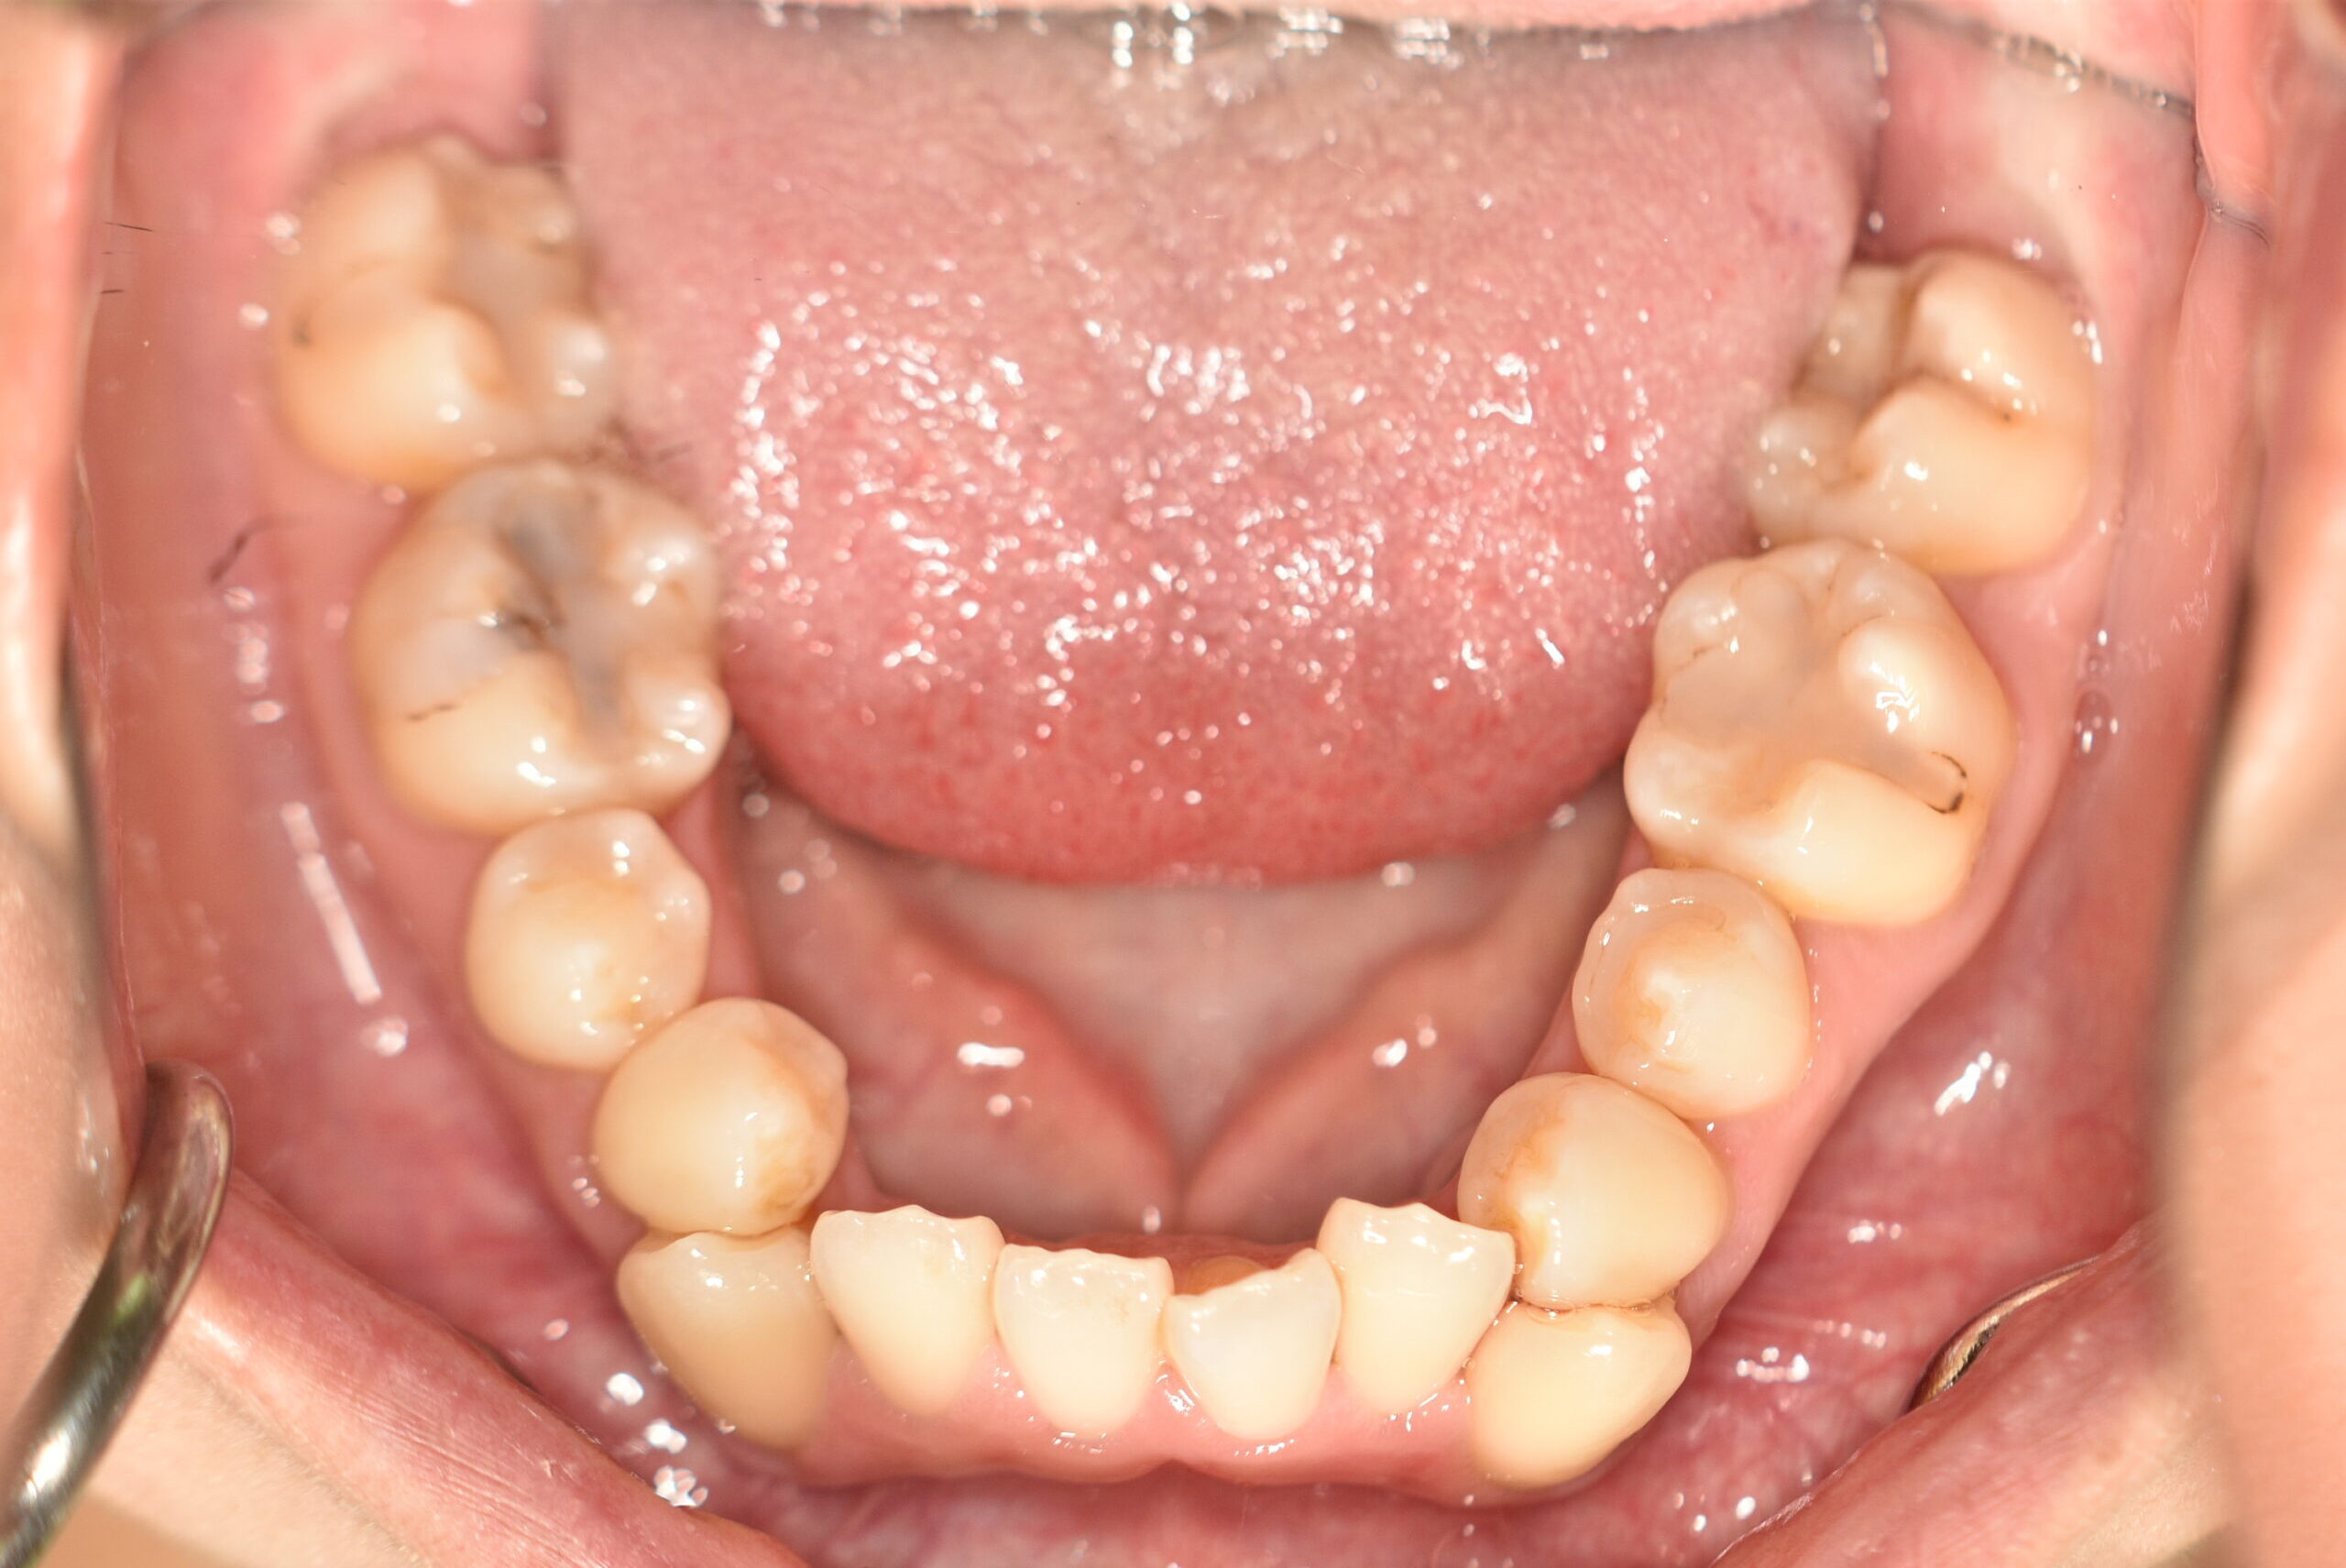

開咬・叢生(抜歯)[2441]

初診時

年齢

26歳6ヶ月 性 別 女性

治療期間 3年7ヶ月 費 用 矯正施術料:1,000,000円 調整料:4,000円/月

治療内容の詳細 初診時26歳の女性で、前歯が噛み合わないことと八重歯を気にされ来院されました。

検査の結果、開咬及び上下顎前歯部叢生を伴うアングルⅢ級不正咬合と診断しました。

治療としては、上顎第一小臼歯、下顎左右犬歯および下顎左右智歯を抜歯し、マウスピース矯正装置(インビザライン)とセルフライゲーションブラケット装置(デーモンシステム)で歯の配列を行いました。

開咬については、顎間ゴムの協力もあり改善されました。

治療期間は、3年7ヶ月でした。